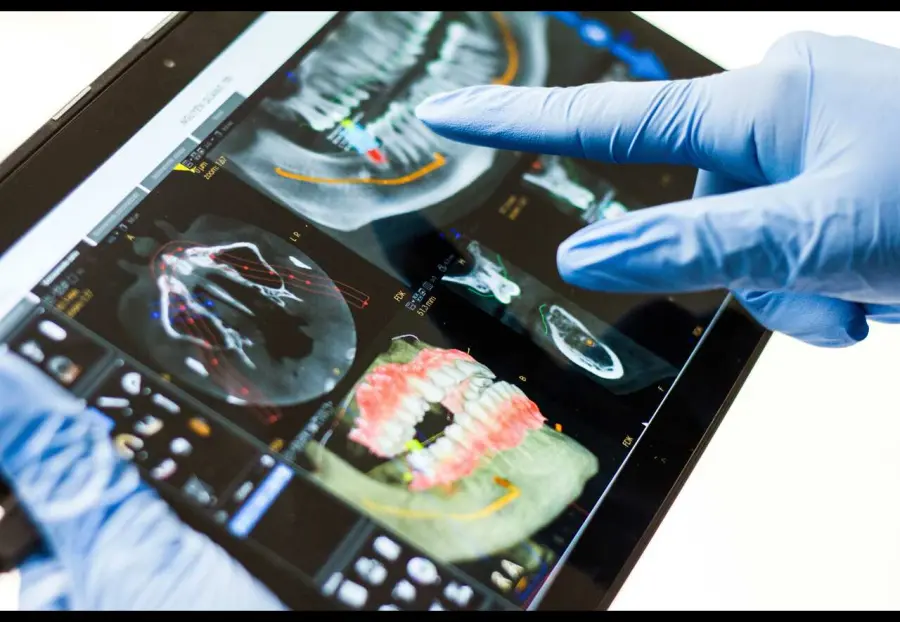

Chirurgia dentale: ecco in cosa consiste e quando si attua

Chirurgia dentale: ecco in cosa consiste e quando si attua

Redazione - April 22, 2024